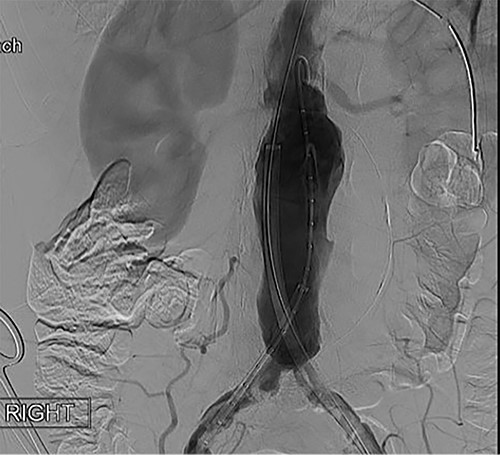

To obtain vascular access, bilateral cutdown technique was used to dissect the common femoral arteries. The femoral arteries were cannulated, the patient heparinized, and an arteriogram obtained (Fig. 2). The main body of the graft was deployed without complication, followed by bilateral iliac limb extensions. The graft was treated with the Molding & Occlusion Balloon (MOB) at all attachment points. Repeat arteriogram demonstrated excellent technical result without evidence of endoleak (Fig. 3). Protamine was administered for reversal of heparin, bilateral groin incisions were closed, and nasogastric tube (NGT) was left in place on low intermittent wall suction. Aspirin/Plavix therapy was continued.

Intraoperative fluoroscopy illustrating infra-renal, abdominal aortic aneurysm prior to graft placement.